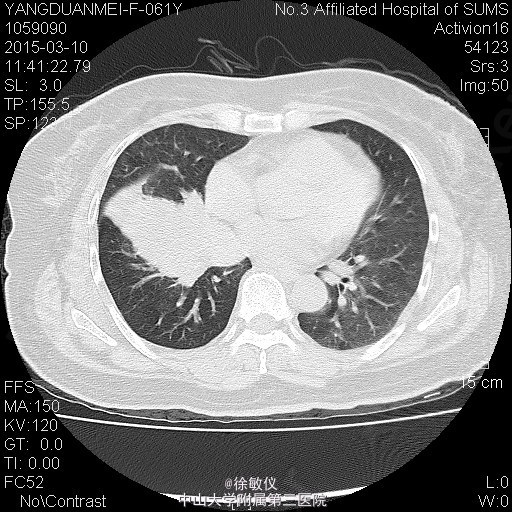

老年女性,主诉:咳嗽2月,胸部CT发现中央型肺癌1天。 现病史:患者2月前无明显诱因出现咳嗽伴胸闷气促,伴少量白色粘液痰,无痰中带血、咯血等不适,当时自行服用“消炎药”治疗(具体不详),2月来症状逐渐加重,至当地医院就诊,查胸部CT提示:右侧中央型肺癌并纵隔淋巴结转移,肝脏考虑转移灶。现为求进一步治疗入院。近期体重减轻2斤。 查体:生命体征平稳,全身浅表淋巴结未扪及肿大。心肺腹查体无特殊。 胸部CT:1、右下中央型肺癌,并右肺门及纵隔多发淋巴结转移;右中间段支气管、中下叶支气管狭窄、闭塞,右肺阻塞性炎症,考虑右侧肺动脉、右下肺静脉受侵。2、肝S4、S8转移瘤。 诊断: 右侧中央型肺癌并肝转移。